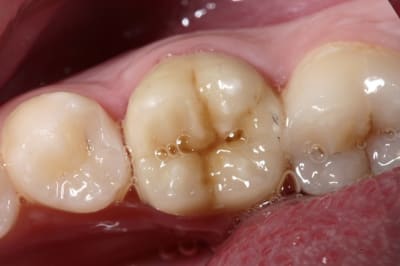

tres joli boulot....

Merci hall, mais là j'y suis pas pour grand-chose ; faut avoir un prothésiste qui maîtrise la céram.

quelle modestie! il fallait un bon dentiste qui fait de belles empreintes à mon avis:-)

On dirait des vraies...

Bravo pour le boulot !